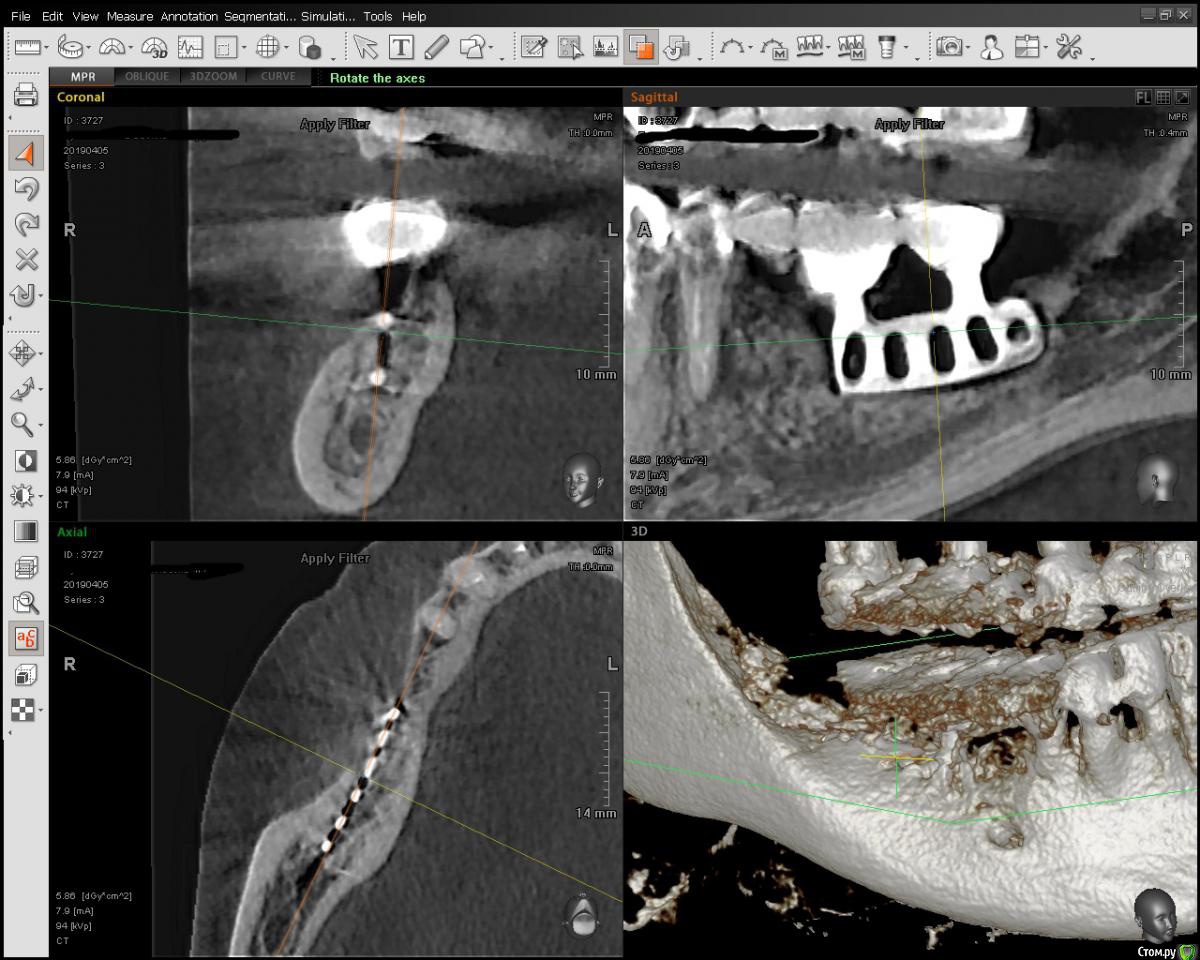

Jurai Опубликовано 6 августа, 2019 Поделиться Опубликовано 6 августа, 2019 Ультрабюджетная по расходнику работа. Лиопласт кортикальный блок, из которого выпилен тонкий ламинат, остатки размолоты в мельнице + ауто, сверху мембрана ТМО Лиопласт, фиксирована только швами к надкостнице. К сожалению, фото операции нет. КЛКТ до и 3 месяца спустя. Как думаете, пора раскрывать или пусть еще? 2 Ссылка на комментарий

Карен Аванесов Опубликовано 20 января, 2021 Поделиться Опубликовано 20 января, 2021 Ультрабюджетная по расходнику работа. Лиопласт кортикальный блок, из которого выпилен тонкий ламинат, остатки размолоты в мельнице + ауто, сверху мембрана ТМО Лиопласт, фиксирована только швами к надкостнице. К сожалению, фото операции нет. КЛКТ до и 3 месяца спустя. Как думаете, пора раскрывать или пусть еще?до.jpgпосле.jpgПолучилось? 1 Ссылка на комментарий